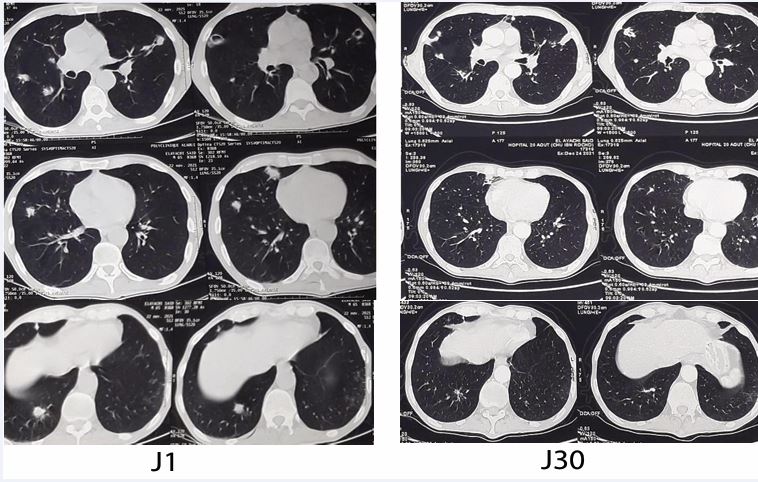

The patient showed favorable clinical and biological improvement, with a decrease in white blood cell count (from 14,530 to 10,760/mm³), neutrophils (from 11,390 to 7,930/mm³), and C-reactive protein (from 45 to 15.3 mg/L), along with an increase in lymphocytes (from 1,070 to 1,492/mm³). Radiological follow-up after one month demonstrated significant regression of pulmonary lesions on CT scan (Figure 3).

Figure 3 CT images showing regression of excavated nodules after one month of Voriconazole treatment.